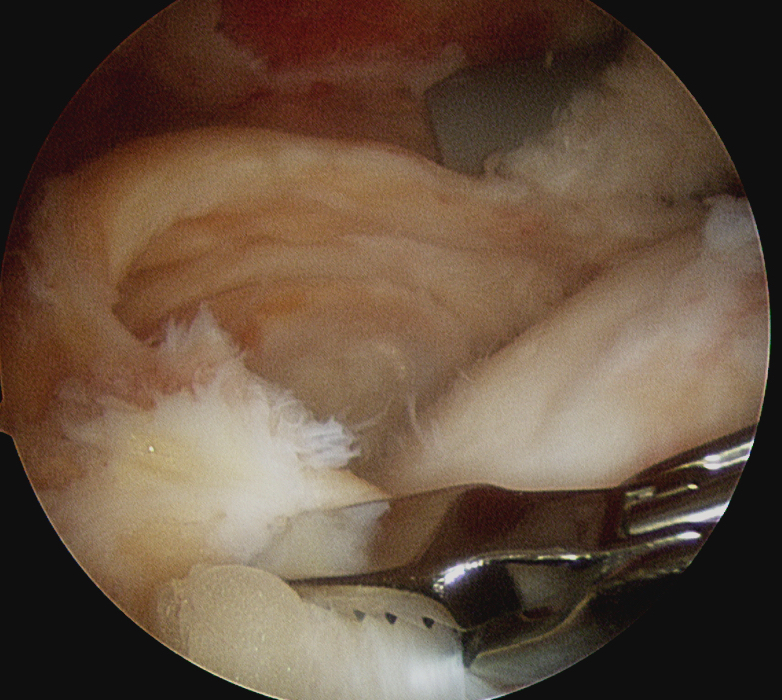

Margin convergence sutures

Release infraspinatus tendon posteriorly and assess mobility

Repair infraspinatus with a combination of margin convergence and posterior suture anchors onto posterior greater tuberosity